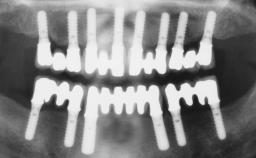

A 63-year-old female patient was referred to the University Medical Center in Groningen, Netherlands, for dental implant treatment. The patient had been edentulous in the upper jaw for 20 years. The remaining teeth in the lower jar had been removed two years before the consultation. The patient was wearing her first maxillary denture and her second mandibular denture; the latter was 1 year old at the time. The conventional upper denture had functioned satisfactorily for many years, but the patient complained about reduced stability and insufficient retention of her lower conventional denture. Her medical history revealed no significant findings. The intraoral examination revealed minor resorption of the maxillary alveolar process and extreme resorption of the mandibular alveolar process.